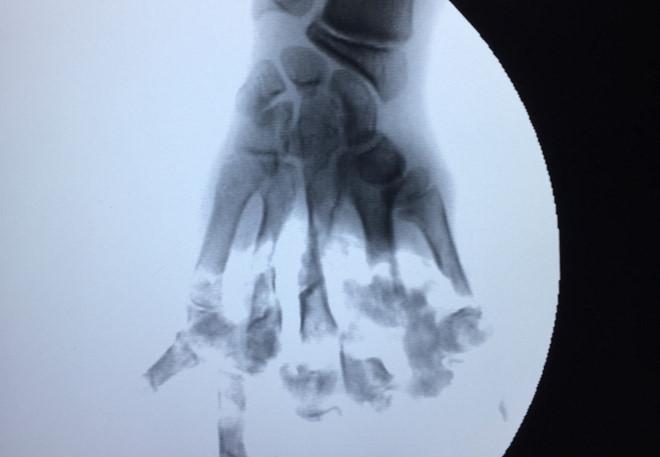

Qua chụp X-quang, cho thấy hình ảnh các đốt xương 5 ngón tay bị nghiền nát, cụt hết xương bàn ngón. Bệnh nhân được chỉ định cắt lọc tạo mỏm cụt 1/2 bàn tay và tiêm thuốc giảm đau.

Hình ảnh phim chụp bàn tay của nạn nhân. Ảnh: Tùng Chi.